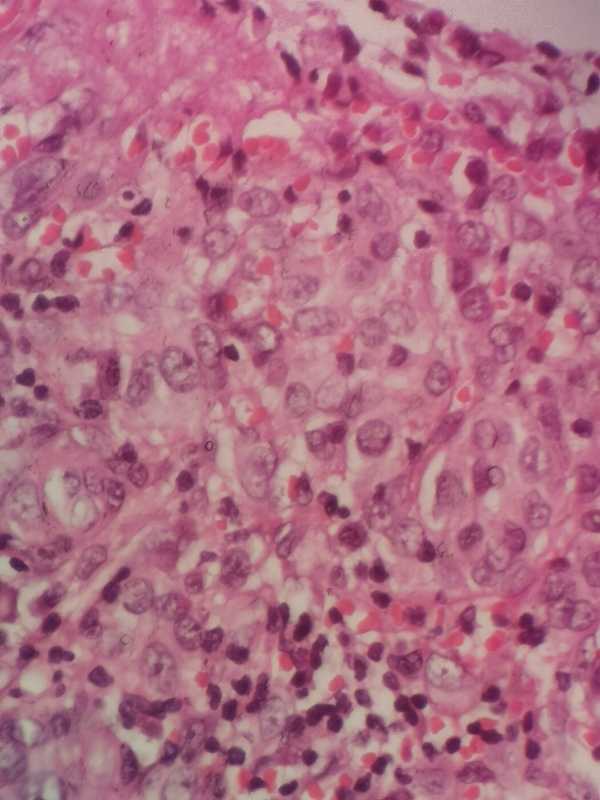

求助各位老师:耳后肿物

性别

男

年龄

64

耳后肿物数年,近来溃破流液

耳后肿物

梭皮一块1.3×0.9×0.5cm,中央皮损区域0.9×0.5,略高出皮表,切面灰粉灰褐 实性 质韧

考虑符合:鳞癌,建议P53.